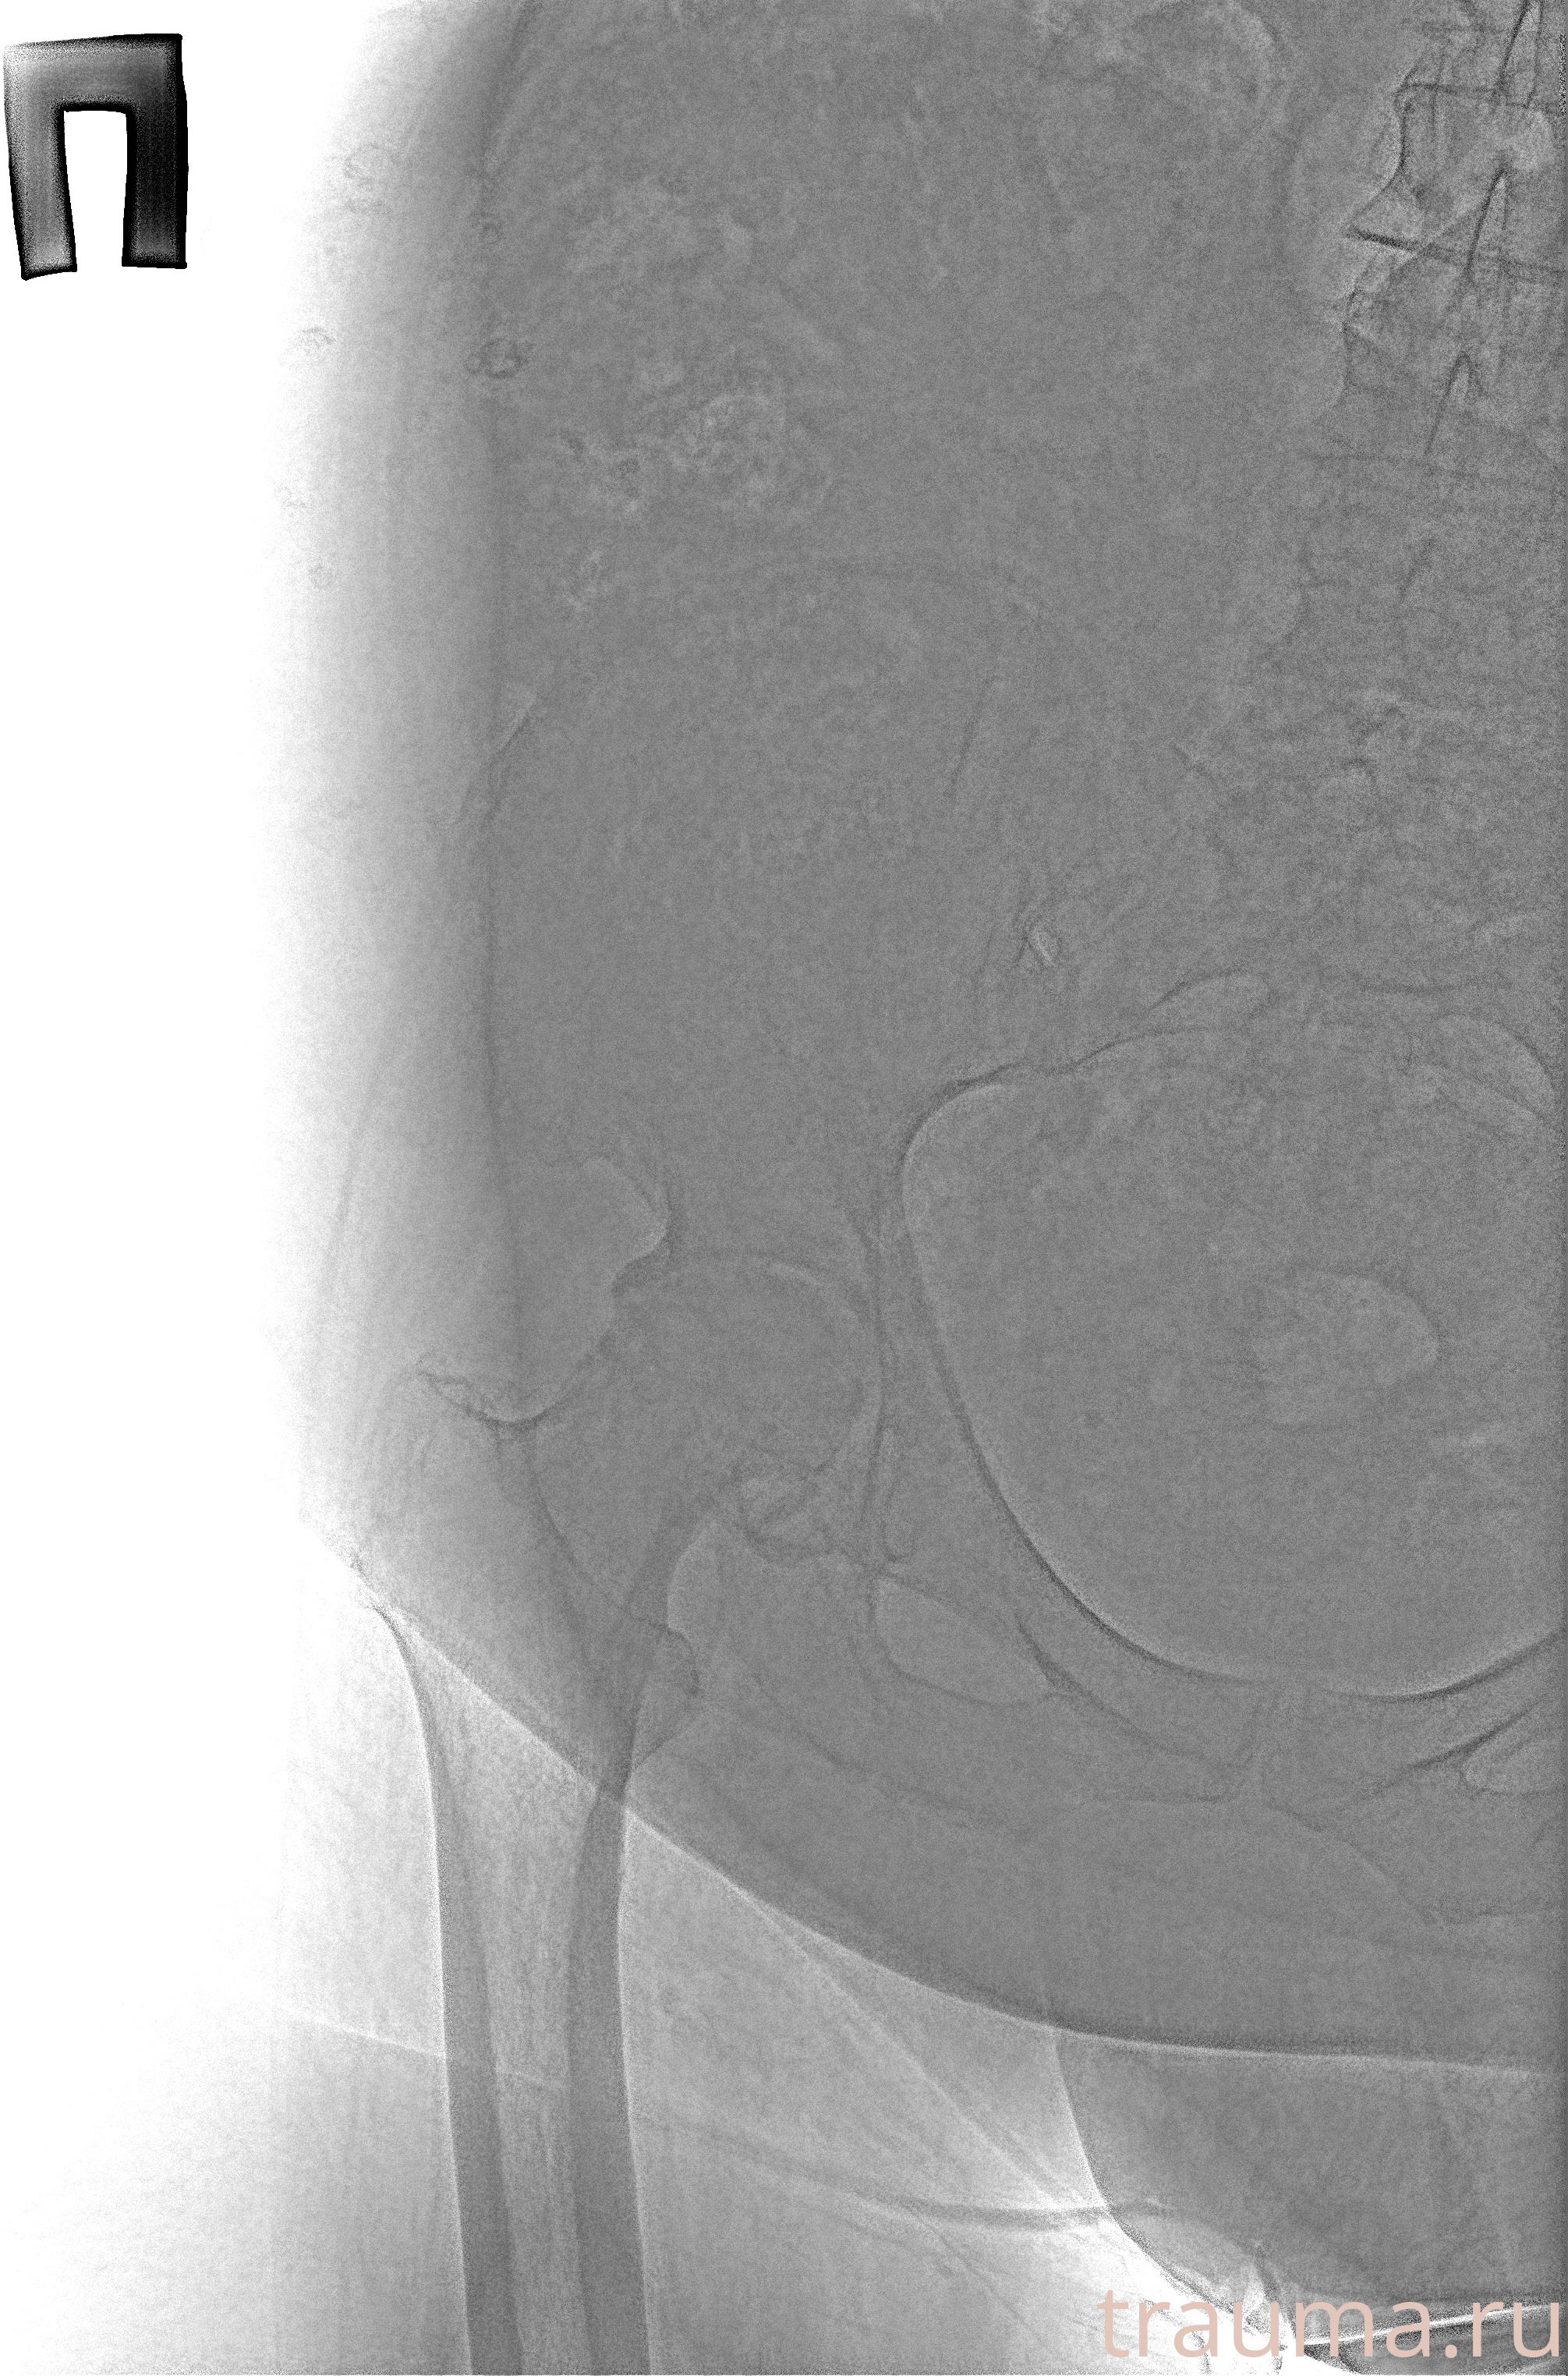

Рентген на дому: по вашему адресу приезжает врач-рентгенолог, травматолог-ортопед с мобильным рентгеновским аппаратом, проводит диагностику травмы или заболевания, делает необходимые рентгенограммы, дает рекомендации по дальнейшему лечению. Получить качественные снимки в домашних условиях возможно благодаря уникальной методике, разработанной МосРентген Центром для института  Склифосовского